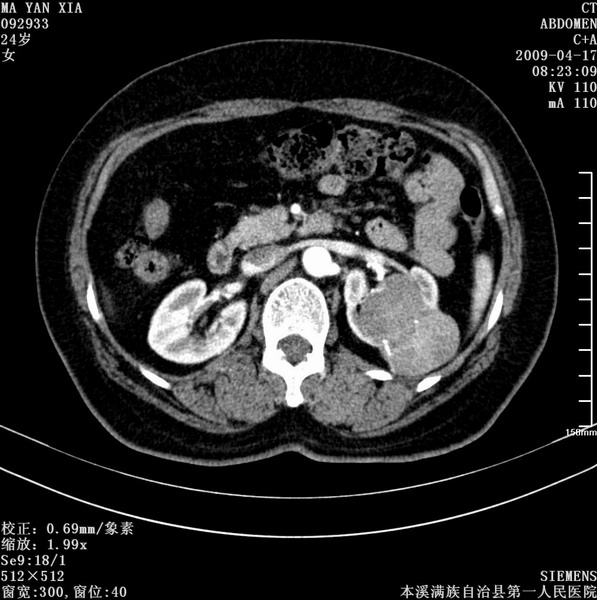

标题: CT19443:肾脏肿瘤两个区强化不一样。 [打印本页]

标题: CT19443:肾脏肿瘤两个区强化不一样。

女,51岁,体检时发现肾脏占位,建议ct增强。无任何自觉症状。

典型的不均匀强化,左肾癌